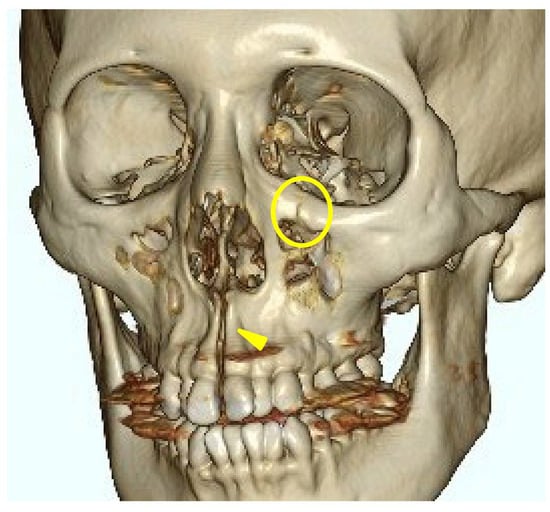

A head CT was performed on the same day. The axial slices revealed a 4 mm wide separation of the midpalatal suture (Figure 3). A fracture of the left maxilla was also observed. The line of this fracture extended from the orbital floor and the anterior surface of the maxilla (Figure 4), starting at the medial edge of the orbital rim, passing through the entire wall of the infraorbital foramen (Figure 5a,b), and reaching the maxilla’s alveolar process.

The trigeminal nerve sensory disturbances observed in this case were likely caused by a fracture within the infraorbital canal and infraorbital foramen, resulting in nerve injury. This is supported by the fact that the symptoms were limited to the region innervated by the infraorbital nerve. The preservation of maxillary molar sensation indicates that the middle superior alveolar branch, which branches off before the infraorbital canal, was not damaged.

In this case, the fracture was concentrated around the zygomatico-maxillary suture for reasons that are unclear; however, there are studies investigating the correlation between the ossification state of facial bone sutures and the effects of rapid maxillary expansion (RME) devices. Provatidis et al. [11] analyzed the effects of RME on the craniofacial complex using finite element modeling, a computer simulation method, by applying RME to a dry human skull. Their analysis revealed that while the lacrimo-maxillary, fronto-maxillary, and naso-maxillary sutures had little influence on RME outcomes, the zygomatico-maxillary suture was significantly affected. In this case, three-dimensional CT reconstruction confirmed that the maxillary expansion was resisted by the surrounding bones, particularly the zygomatic bones, leading to the observed fracture. This finding suggests that, unlike in SARPE, where osteotomies reduce skeletal resistance, MARPE encounters direct resistance from surrounding craniofacial structures. Consequently, stress is concentrated at certain anatomical sites, potentially increasing fracture risk. This observation aligns with the finite element analysis by Provatidis et al., which demonstrated that the zygomatic bones serve as the primary limitation to maxillary expansion rather than the nasal or frontal bones. The presence of a fracture in the infraorbital region further supports this idea, as trauma-induced zygomatic fractures frequently involve fracture lines passing through the infraorbital foramen, leading to sensory disturbances similar to those observed in this case. Previous studies on trauma-induced zygomatic fractures have reported that fracture lines frequently pass through the infraorbital foramen, leading to sensory disturbances of the second branch of the trigeminal nerve, which are typical symptoms of such fractures [12,13]. The presence of a fracture in the infraorbital region in this case suggests that a similar mechanism may have contributed to MARPE-induced fractures, as the infraorbital foramen is inherently a site prone to fractures caused by external forces.

Figure 5. The axial view of the facial bone computed tomography at the level of the infraorbital canal. (a) A fracture line passing through the infraorbital canal is observed between the two yellow triangle markers. (b) A fracture line along the infraorbital canal is observed extending posteriorly to the orbital floor (yellow triangle marks).